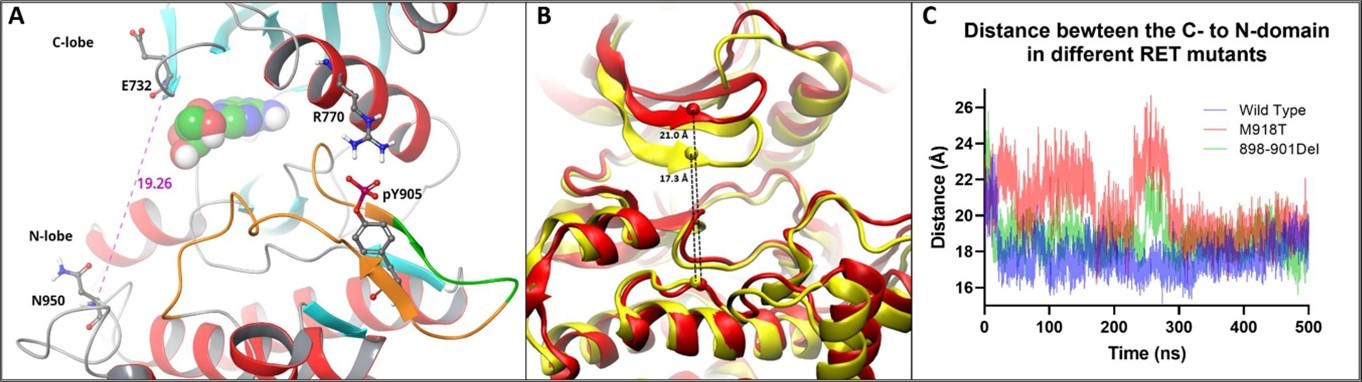

Canonical kinase activation requires phosphorylation of Ser, Thr, and Tyr residues in the activation loop, which leads to its fixation in the outward position, thus enabling substrate binding. The RET 898-901 deletion mutation is located at the tip of the activation loop (Figure 3A). To assess the impact of the deletion mutation on RET kinase structure, we built an in-silico homology model of the mutant and performed molecular dynamics simulation of the 898-901del mutant, M918T mutant, and wild type (WT) kinase. The overall conformation of all three proteins was very similar. The differences we found is with the accessibility of the ATP binding site located between the N- and C- domains. We monitored the distance between the N- and C- domains by measuring distance between Cα atoms of Glu732 and Asn950 (Figure 3B). Simulations started with kinases in the ‘open’ ATP accessible conformation which measured 19.3Å and were run for 500 nanosecond (NS). In the WT simulation, we observed faster collapse of the ATP binding site which remained closed during the entire 500ns of the simulation (Figure 3C). This is reflected by the shortened distance between residues from the N- and C- domains to from 17.3Å at 250ns. In the deletion and M918T mutants, we observed an initial collapse of the ATP site, similar to the wild type. However, in the deletion mutant, at 250ns, the Glycine Rich Loop of the N-domain shifted away from the C-domain measuring 21Å, yielding access to the ATP site (open conformation). This shift from closed to open conformation was also seen in the M918T mutant, measuring 24Å at 250ns. The effect of increased ATP site accessibility correlates with the mechanism of malignant kinase activation, further supporting our hypothesis of the malicious nature of this mutation.

Figure 3.Molecular dynamic modeling of the RET 898-901Del mutation. Amino acids 898-901 (highlighted in green) are found within the activation loop (highlighted in orange) of the RET kinase A. The activation loop mediates the ‘open’ and ‘closed’ conformations of RET kinase by forming hydrogen bonds with the phosphorylated Y905 and the alpha helix of the C-domain. Phosphorylated Y905 stabilizes the ‘open’ conformation allowing ATP to bind between the C- and N-domains. The distance between the α carbon of amino acid E732 in the C-domain and N950 in the N-domain was used to track the conformational changes of kinase. The activate phosphorylated WT kinase had an N- to C-domain distance of 19.3Å. A 500ns molecular dynamic simulation was performed with WT, 898-901Del, and M918T RET kinases in the ‘open’ conformation with no phosphorylation in the activation loop. The difference in N- to C- domain distance in the deletion mutant (red) and WT (yellow) at 250ns was 4 Å, measuring 21Å (‘open’ conformation) and 17.3Å (‘closed’ conformation) respectively B. The distance between the C- to N-domains was tracked throughout the entire 500ns simulation showing that the 898-901 deletion mutant (green) and M918T mutant (red) had a larger overall distance between the C- and N-domains, compared to the wild type (blue) C. Additionally, the deletion and M918T mutants freely switch between the open and closed conformations. The WT kinase was unable to re-enter the open conformation, due to a lack of phosphorylation within the activation loop.

In Silico molecular dynamic simulations have demonstrated that the RET 898-901Del mutant destabilizes the ‘closed’ inhibitory activation loop conformation, favoring an ‘open’ active conformation sensitive to Pralasetinib. This RET deletion mutation is a pathogenic mutation with comparable enzymatic activity to the more common RET M918T mutation. The case report highlights the versatility of structural biologic approaches to guide therapeutic decisions.